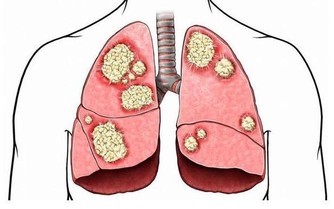

4.全身因素:一些全身的疾病如:

A. 血脂過高: 長期血脂過高, 易引起血管壁硬化, 加上血脂過高, 血液粘稠, 血流變慢, 細胞所得到氧氣養料減少,導致麻木.

B. 糖尿病人: 血糖維持較高水平, 長久以往, 對人體血管, 神經造成極大傷害, 血管硬化, 神經變性.